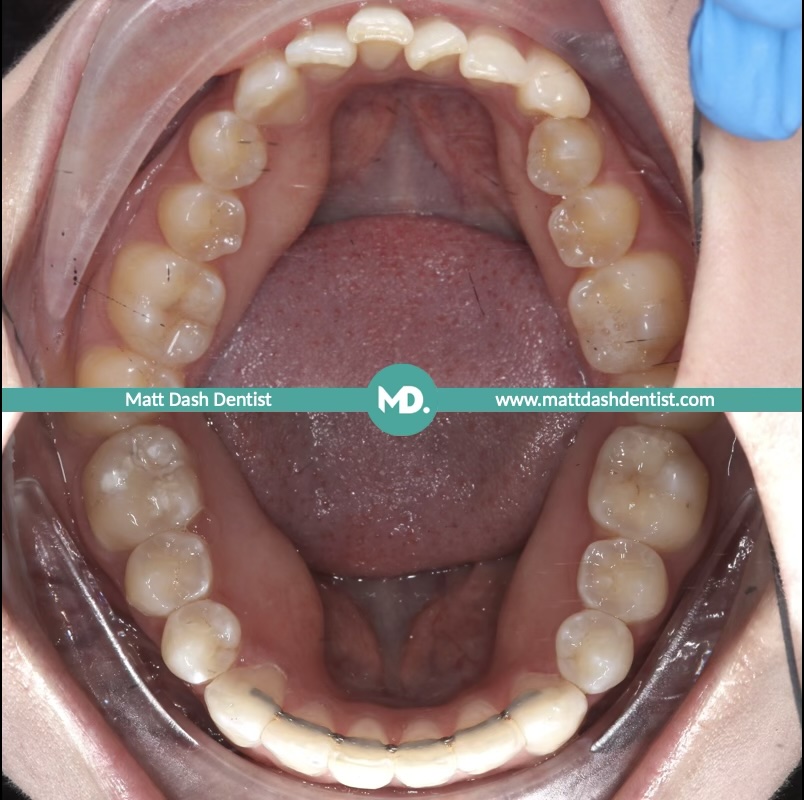

During a routine check up recently, I discussed bite stability with a regular patient. She had some tooth misalignment and rotations. While these did not bother her aesthetically, they were causing early signs of tooth wear around her lower incisors and canines.

When teeth are misaligned, your bite may be uneven. This means certain teeth take more force than they are designed to handle when you chew or close your mouth. Over time, this uneven pressure can cause the enamel to wear down, leaving teeth looking shorter and potentially feeling more sensitive.

To achieve a stable, even bite, we provided Invisalign treatment. The goal was to realign the teeth so that the biting forces were distributed safely and evenly across the whole mouth.

Realigning teeth is only the first step. To ensure the bite remains stable and the teeth are protected from future wear, maintenance is essential. Following her Invisalign treatment, we placed fixed retainers on both the upper and lower arches, alongside providing removable night time retainers. This system ensures the bite remains predictable for years to come.